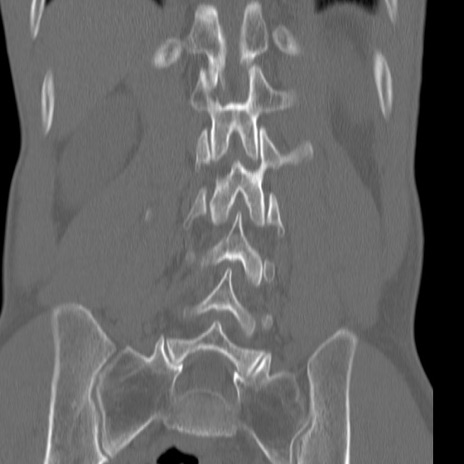

症例3 腰椎CT(冠状断像)

【症例】30歳代男性

【主訴】腰痛

【現病歴】本日旅行先で観光中に、友人と衝突し転倒し受傷。

【身体所見】麻痺なし、右下腿内側前面外側、左下腿内側に知覚鈍麻・しびれ

異常所見と診断は?

腰椎CT